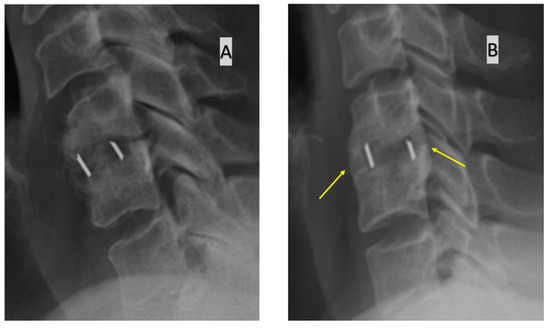

- bone bridging visible on the anterior and/or posterior edge of the operated disc space in a lateral radiograph. Fusion is diagnosed when bone bridging is visible, and if it is not visible, a pseudoarthrosis is diagnosed.